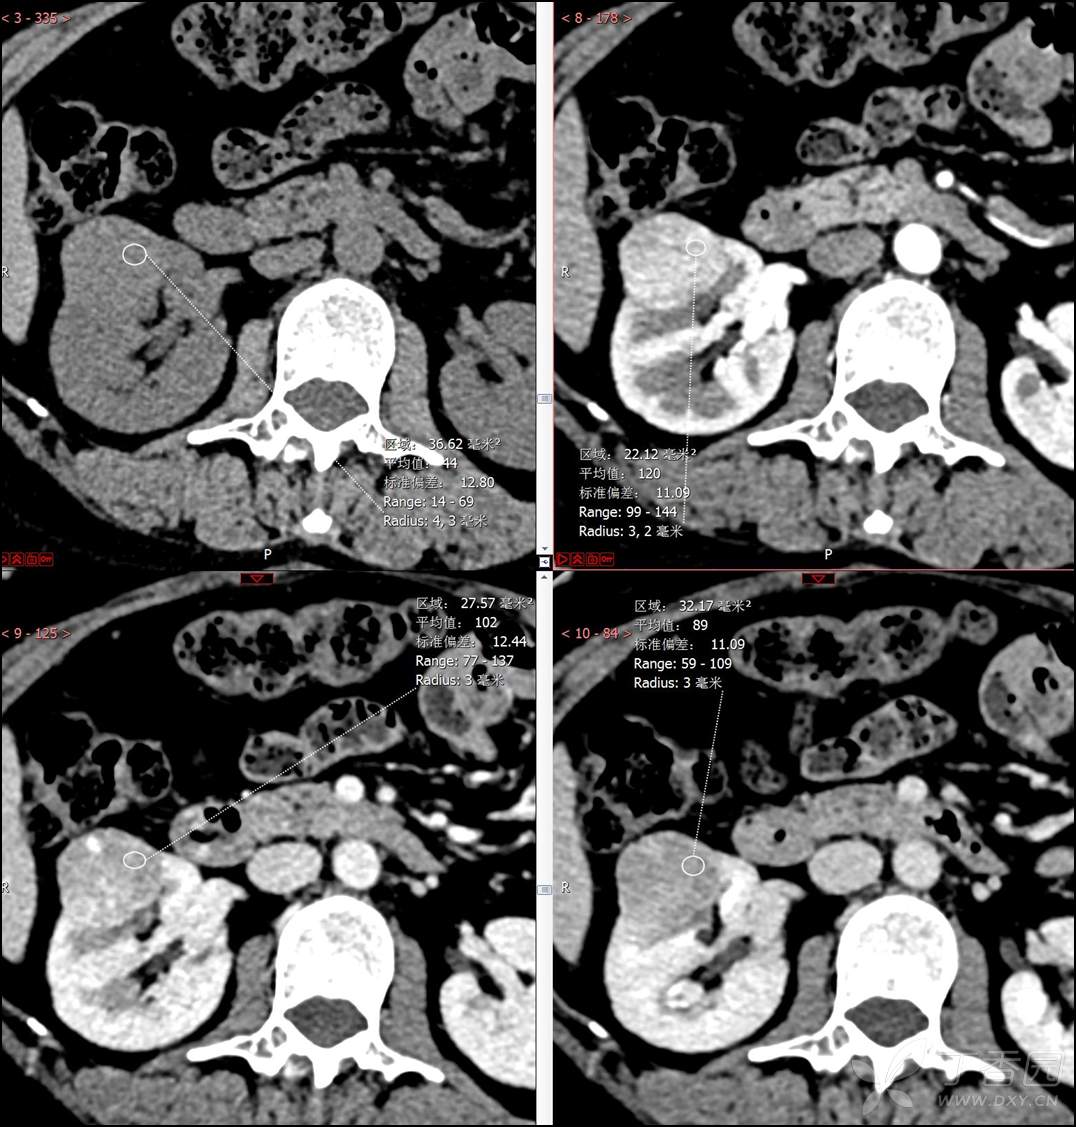

【影诊笔记516】中年女性,检查发现肾占位2周就诊~『嗜酸细胞腺瘤』

主诉:检查发现肾占位2周

简要病史:患者2周前体检发现肾实质性占位,无腰痛,无血尿,无尿频、尿急、尿痛,无发热,在外未行特殊治疗。患者为行进一步治疗就诊于我院,门诊以“肾占位性病变 ”收入我科,患者自发病以来,神志清,精神可,小便如上所述,大便正常,体重无显著变化。